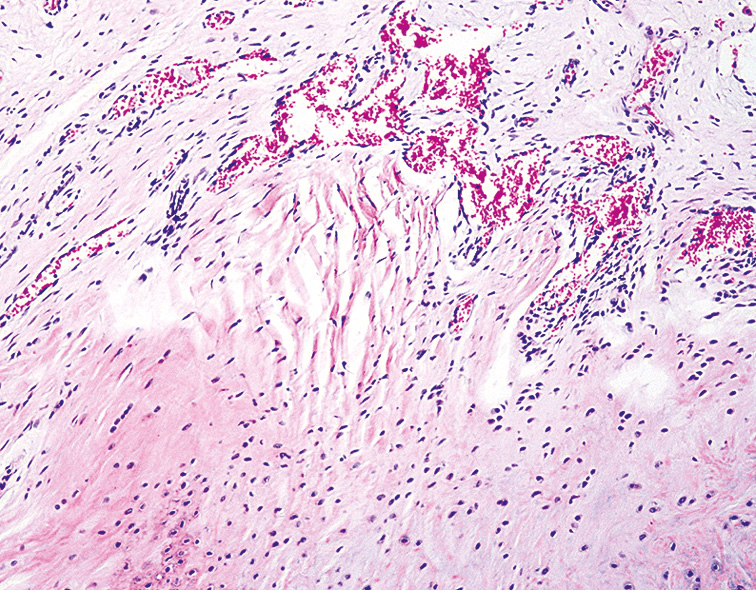

Проведенные гистологические исследования СОП животных опытной группы через 7 мес после ДМГ поражения позволили выявить глубокие деструктивно-дегенеративные изменения всех ее компонентов. Так, среди фрагментов гиалиново-волокнистой хрящевой ткани отмечались скопления фиброретикулярных клеток костного мозга с примесью жировых включений, а также опухолевые клетки (рис. 7). В этот же срок эксперимента для тканей СОП животных были характерны элементы костного мозга в прослойках хрящевой ткани, что приводило к утолщению стромальной соединительной ткани и фиброзу (рис. 8).

Рис. 8. Слизистая оболочка пасти животного (опытная группа) через 7 мес от начала эксперимента. Окраска гематоксилином и эозином, ×180

Fig. 8. The mucous membrane of the animal’s mouth (experimental group). after 7 months from the beginning of the experiment. Staining with hematoxylin and eosin, ×180.